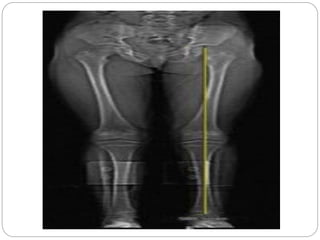

The most accurate method to identify leg (limb) length

inequality (discrepancy) is through radiography.

Radiography: Limitations are an inherent inaccuracy in

patients with hip or knee flexion contracture.

However, radiography has to be performed by a

specialist, takes more time and is costly. It should only

be used when accuracy is critical.

Scan method ( x-ray)

 Not available without professional medical

equipment. This methods involves scanning the pelvis

and legs and with the use of computer technology, the

images are enlarged to measure the distance

between reference points (again, usually the pelvis

and ankle joints), with very high accuracy.